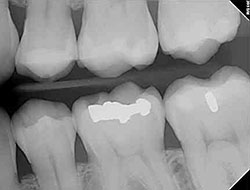

Digital X-Rays

Using the most advanced dental technology possible is just as important as staying up-to-date on the latest treatment techniques. Because our practice is dedicated to providing you with the safest and most convenient treatment options available, we utilize advanced digital X-ray technology in our office.

Digital X-rays provide several advanced imaging options, designed to save time, provide clearer dental photos, and expose patients to less radiation than with traditional X-ray technology.

Our practice is focused on making your dental experience as comfortable as possible. At your next appointment, we’ll be happy to answer any questions you may have.